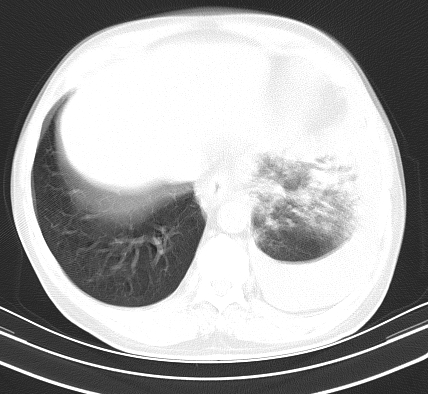

以下是引用老爱克斯新网客在2008-7-31 6:30:00的发言:[br]左肺上叶大片状病灶,左肺上叶支气管狭窄呈鼠尾状,左肺门增大,纵隔内见肿大淋巴结,左侧胸腔积液,余肺清晰。左肺中心型肺癌淋巴结转移,

以下是引用zjb在2008-7-31 6:32:00的发言:[br]左侧中心性肺癌 阻塞性肺炎 肺不张 胸腔积液 建议气管镜

以下是引用zjzjr在2008-7-31 8:45:00的发言:[br]考虑左侧中心性肺癌伴阻塞性肺炎,左肺上叶肺不张,纵隔淋巴结转移;左侧胸腔积液。建议行纤支镜检查。

以下是引用sdzyy在2008-7-31 8:47:00的发言:[br]病灶较治疗前有所进展,胸水增多, 左侧中心性肺癌 并 阻塞性肺炎 肺不张 胸腔积液 可能性大; 建议气管镜检查。 [br] [br]